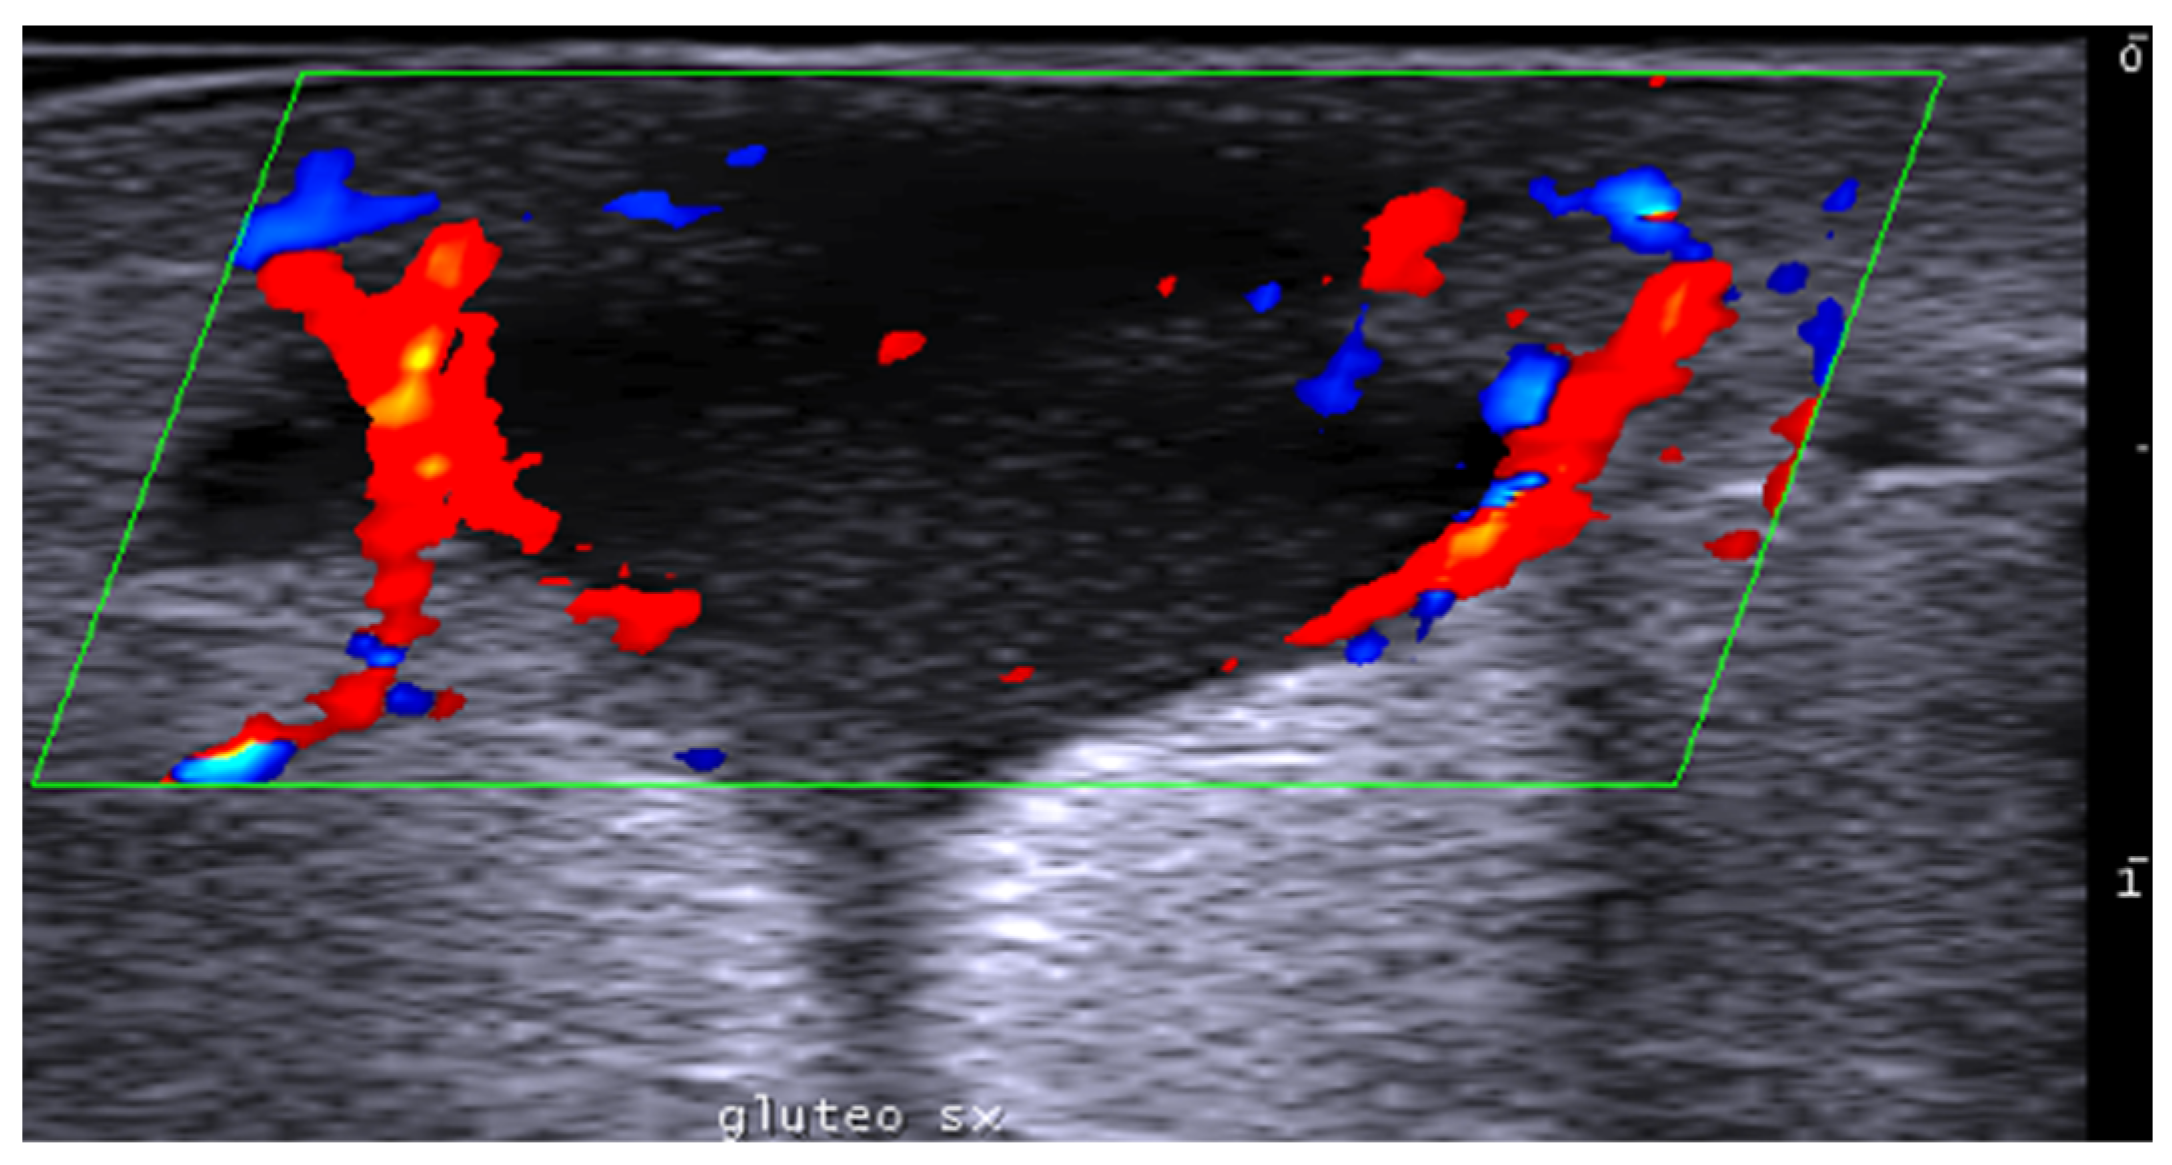

- Del Vecchio, D.; Kenkel, J.M. Practice Advisory on Gluteal Fat Grafting. Aesthetic Surg. J. 2022, 42, 1019–1029. [Google Scholar] [CrossRef]

- Tillo, O.; Nassab, R.; Pacifico, M.D. The British Association of Aesthetic Plastic Surgeons (BAAPS) Gluteal Fat Grafting Safety Review and Recommendations. Aesthetic Surg. J. 2023, 43, 675–682. [Google Scholar] [CrossRef] [PubMed]

- Vidal-Laureano, N.; Huerta, C.T.; Perez, E.A.; Earle, S.A. Augmented Safety Profile of Ultrasound-Guided Gluteal Fat Transfer: Retrospective Study with 1815 Patients. Aesthetic Surg. J. 2024, 44, NP263–NP270. [Google Scholar] [CrossRef] [PubMed]

- Elsaftawy, A.; Ostrowski, P.; Bonczar, M.; Stolarski, M.; Gabryszuk, K.; Bonczar, T. Buttock Augmentation with Ultrasonic Liposuction and Ultrasound-Guided Fat Grafting: A Retrospective Analysis Based on 185 Patients. J. Clin. Med. 2024, 13, 1526. [Google Scholar] [CrossRef]

- Elsaftawy, A.; Ostrowski, P.; Bonczar, M.; Stolarski, M.; Gabryszuk, K.; Bonczar, T. Enhancing Buttock Contours: A Safer Approach to Gluteal Augmentation with Ultrasonic Liposuction, Submuscular Implants, and Ultrasound-Guided Fat Grafting. J. Clin. Med. 2024, 13, 2856. [Google Scholar] [CrossRef]

- Wang, B.; He, P.; Zhao, R. B-ultrasound-assisted gluteal fat grafting in Asians: A prospective study of quantitative results from three-dimensional imaging and B-ultrasound analysis. J. Plast. Reconstr. Aesthetic Surg. 2024, 94, 12–19. [Google Scholar] [CrossRef] [PubMed]